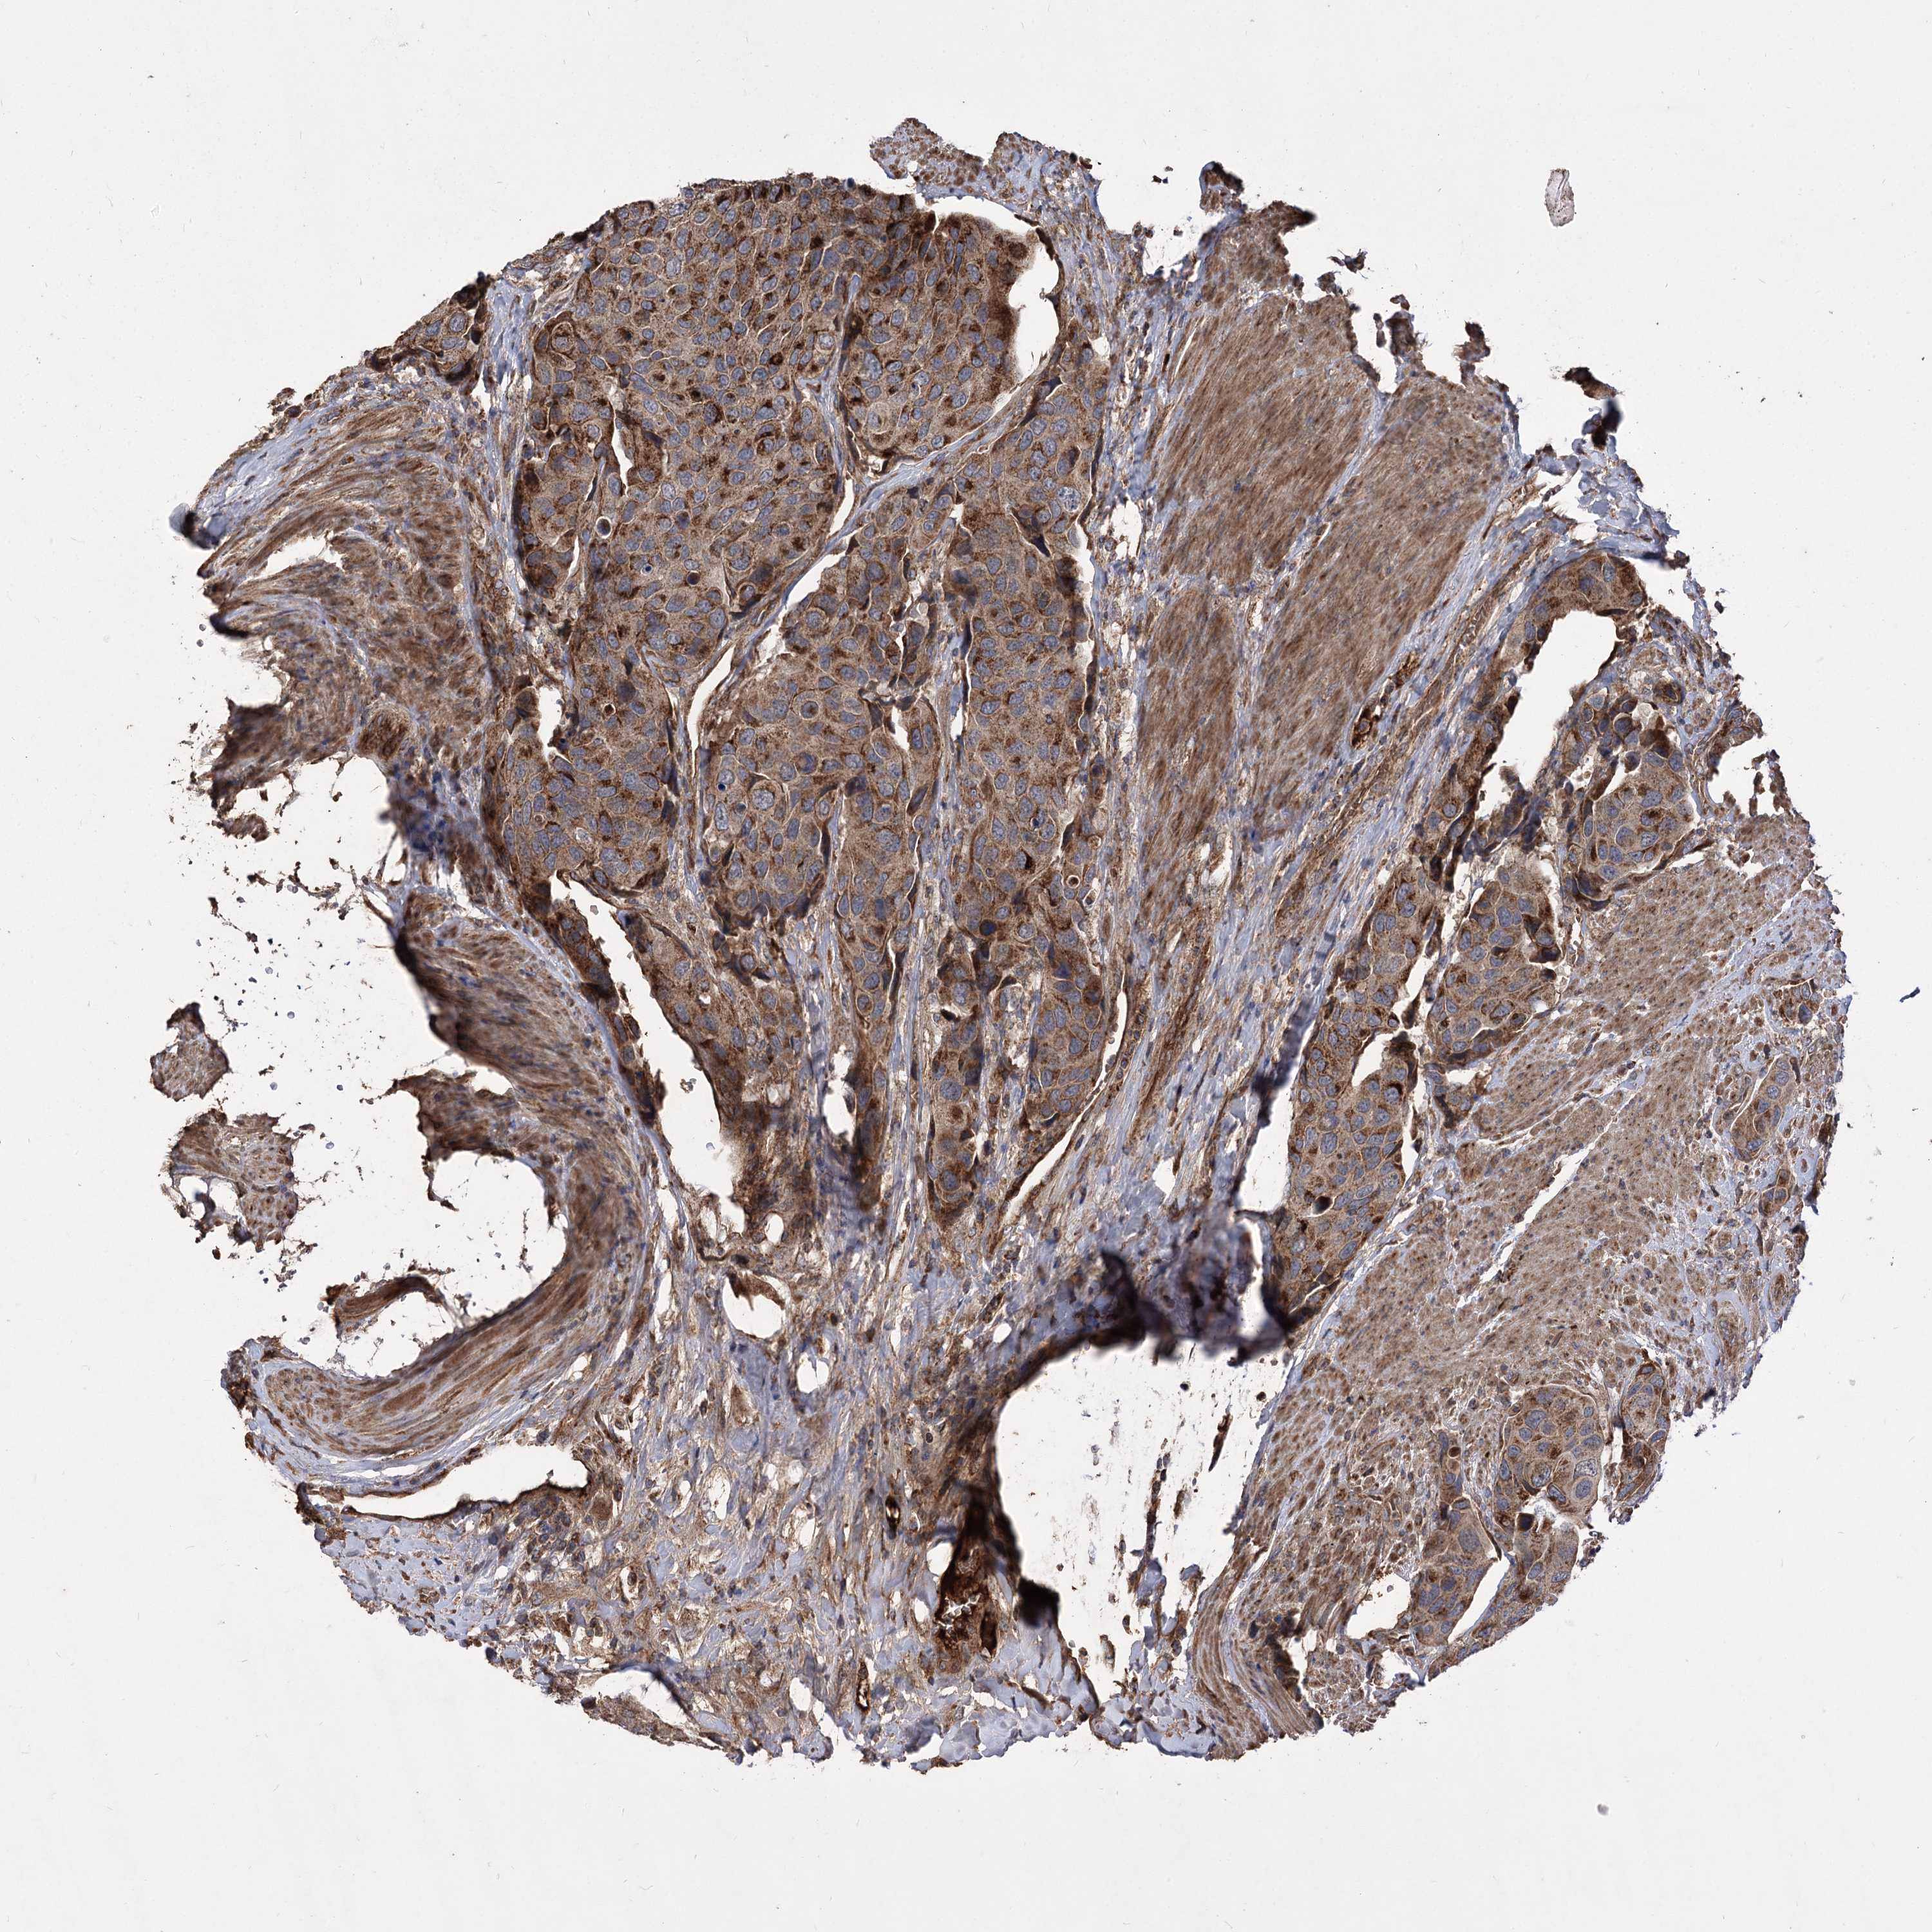

UROTHELIAL CANCER - Protein expressioni

A mouse-over function shows sample information and annotation data. Click on an image to view it in a full screen mode. Samples can be filtered based on level of antibody staining by selecting one or several of the following categories: high, medium, low and not detected. The assay and annotation is described here.

Note that samples used for immunohistochemistry by the Human Protein Atlas do not correspond to samples in the TCGA dataset.

Antibody stainingi

Antibody staining in the annotated cell types in the current human tissue is reported as not detected, low, medium, or high, based on conventional immunohistochemistry profiling in selected tissues. This score is based on the combination of the staining intensity and fraction of stained cells.

Each image is clickable and will lead to virtual microscopy that enables deeper exploration of all samples and also displays staining intensity scores, fraction scores and subcellular localization as well as patient and tissue information for each sample.

Antibody HPA038469

Antibody CAB022664

Antibody CAB034035

Staining

High

Medium

Low

Not detected

Intensity

Strong

Moderate

Weak

Negative

Quantity

>75%

75%-25%

<25%

None

Location

Nuclear

Cytoplasmic/membranous

Cytoplasmic/membranous,nuclear

Urothelial carcinoma, High grade

Urothelial carcinoma, Low grade